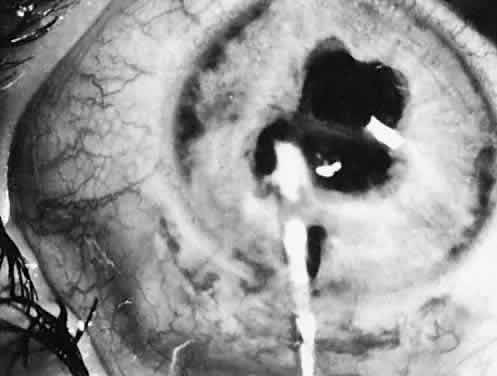

Failure of a pupil to dilate fully is common because of the presence of synechiae (Fig. 9) or relatively atonic pupillary dilator muscles (rubella and Marfan's). If the pupil is small or synechiae are noted, the location of the incision can be adjusted or a paracentesis tract or tracts can be placed to allow iris manipulation with instruments or the insertion of iris retracting hooks. If the pupil is 2 mm or smaller, a sphincterotomy may be necessary. This procedure can be accomplished by cutting the iris sphincter with a suction cutting instrument or a Vannas scissors.

Fig. 9. A cataract that resulted from repeated episodes of uveitis. The pupil will not dilate because of lens-iris synechiae.